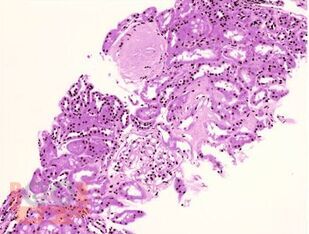

Учебное пособие посвящено клинико-морфологическим аспектам классификации и диагностики амилоидоза с использованием современных методов морфологии и иллюстративного материала. В пособии представлены краткий теоретический материал, ситуационные задачи с примерами решения и для самостоятельного выполнения, тестовые задания и ответы на них, что позволит студентам проводить диагностику амилоидоза с целью установления диагноза, способствует оценке морфофункциональных, физиологических состояний и патологических процессов в организме человека для решения профессиональных задач.